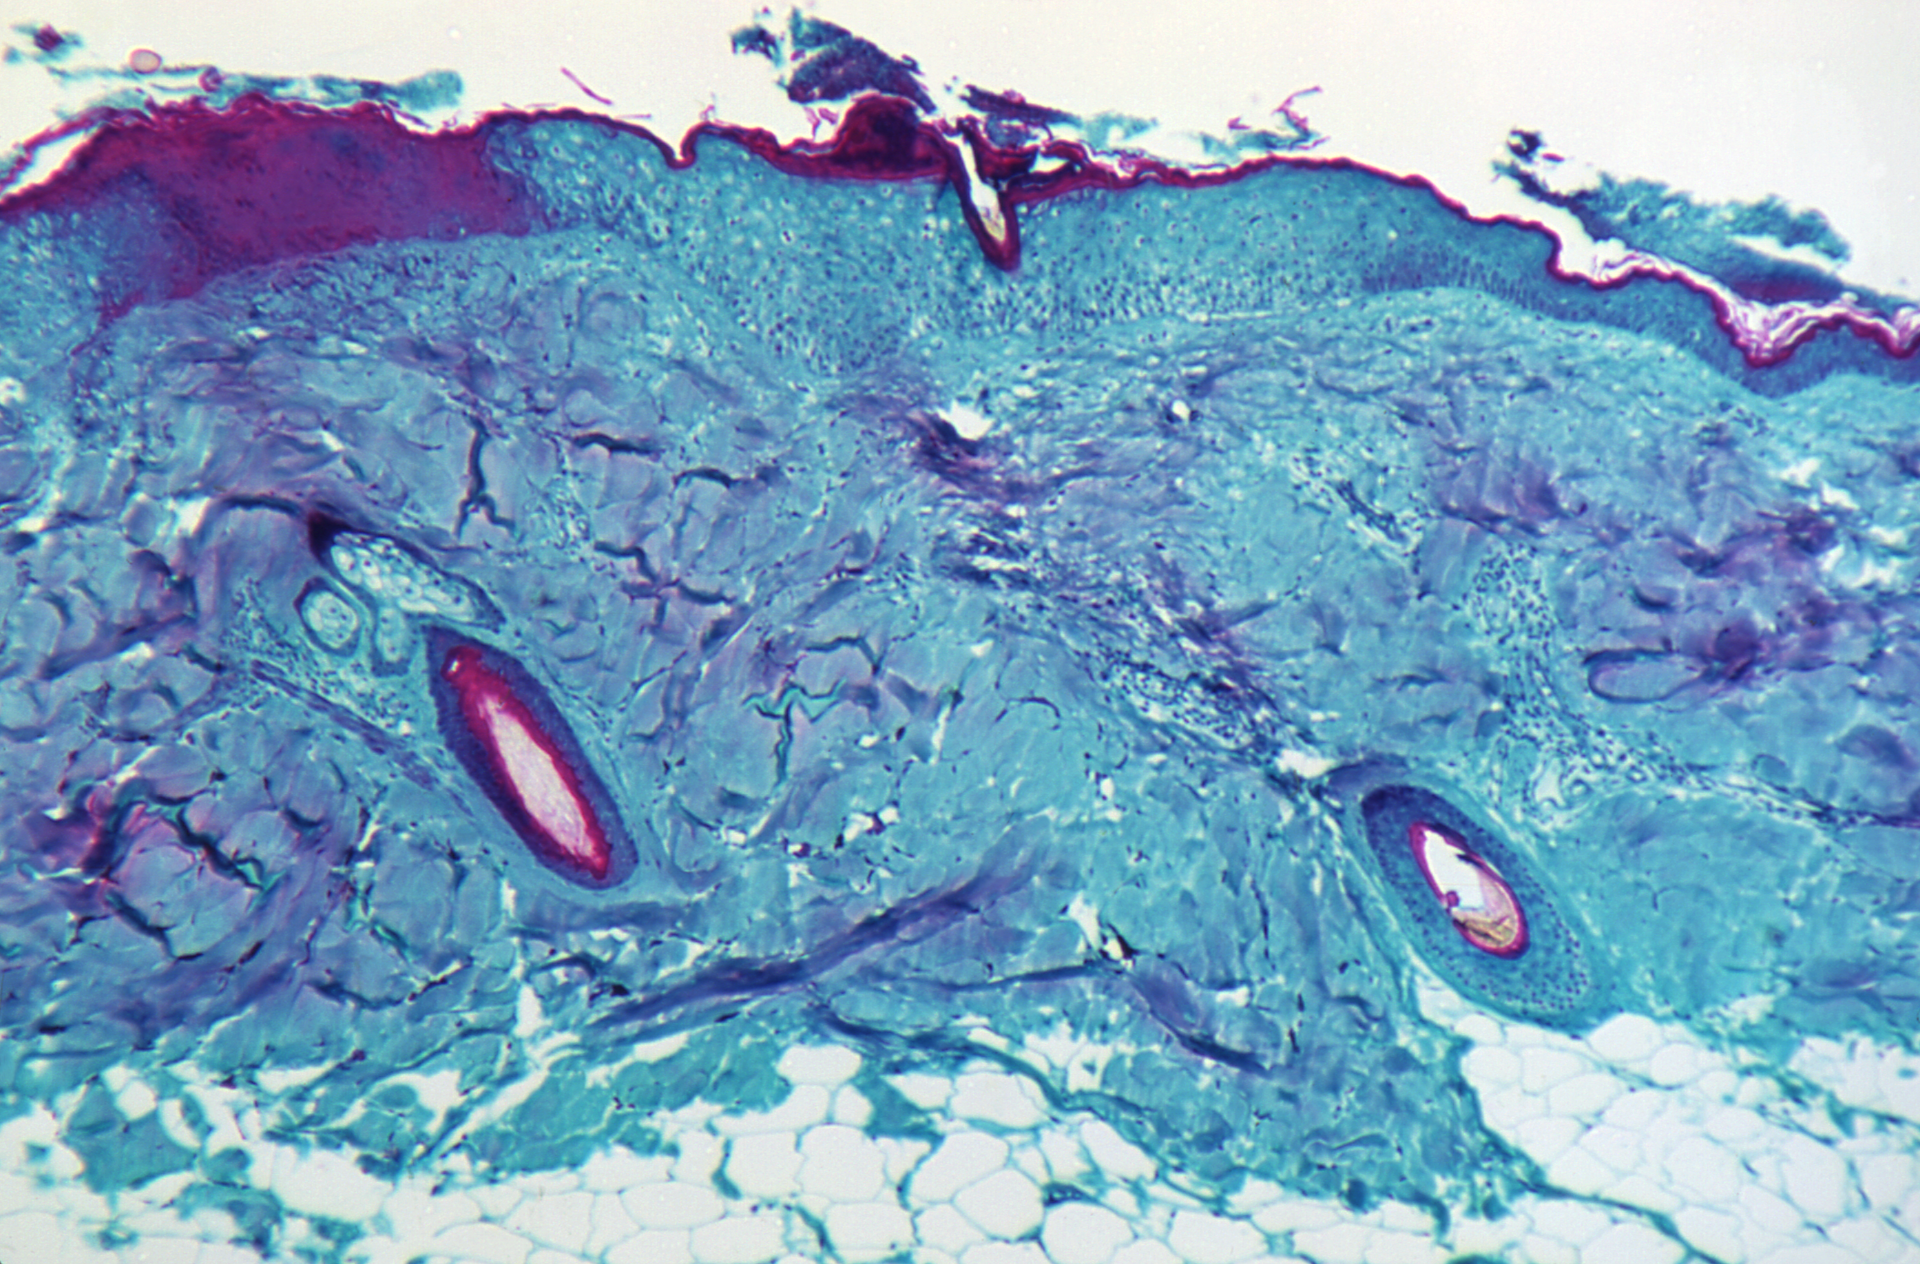

Initial symptoms are fever, headache and swollen lymph nodes. This is followed by a rash. The rash initially consists of flat patches. It then progresses to raised nodules and then to vesicles, with one to two days in each phase. The final stage of pus-filled blisters can last five to seven days. The rash heals by scabbing over.